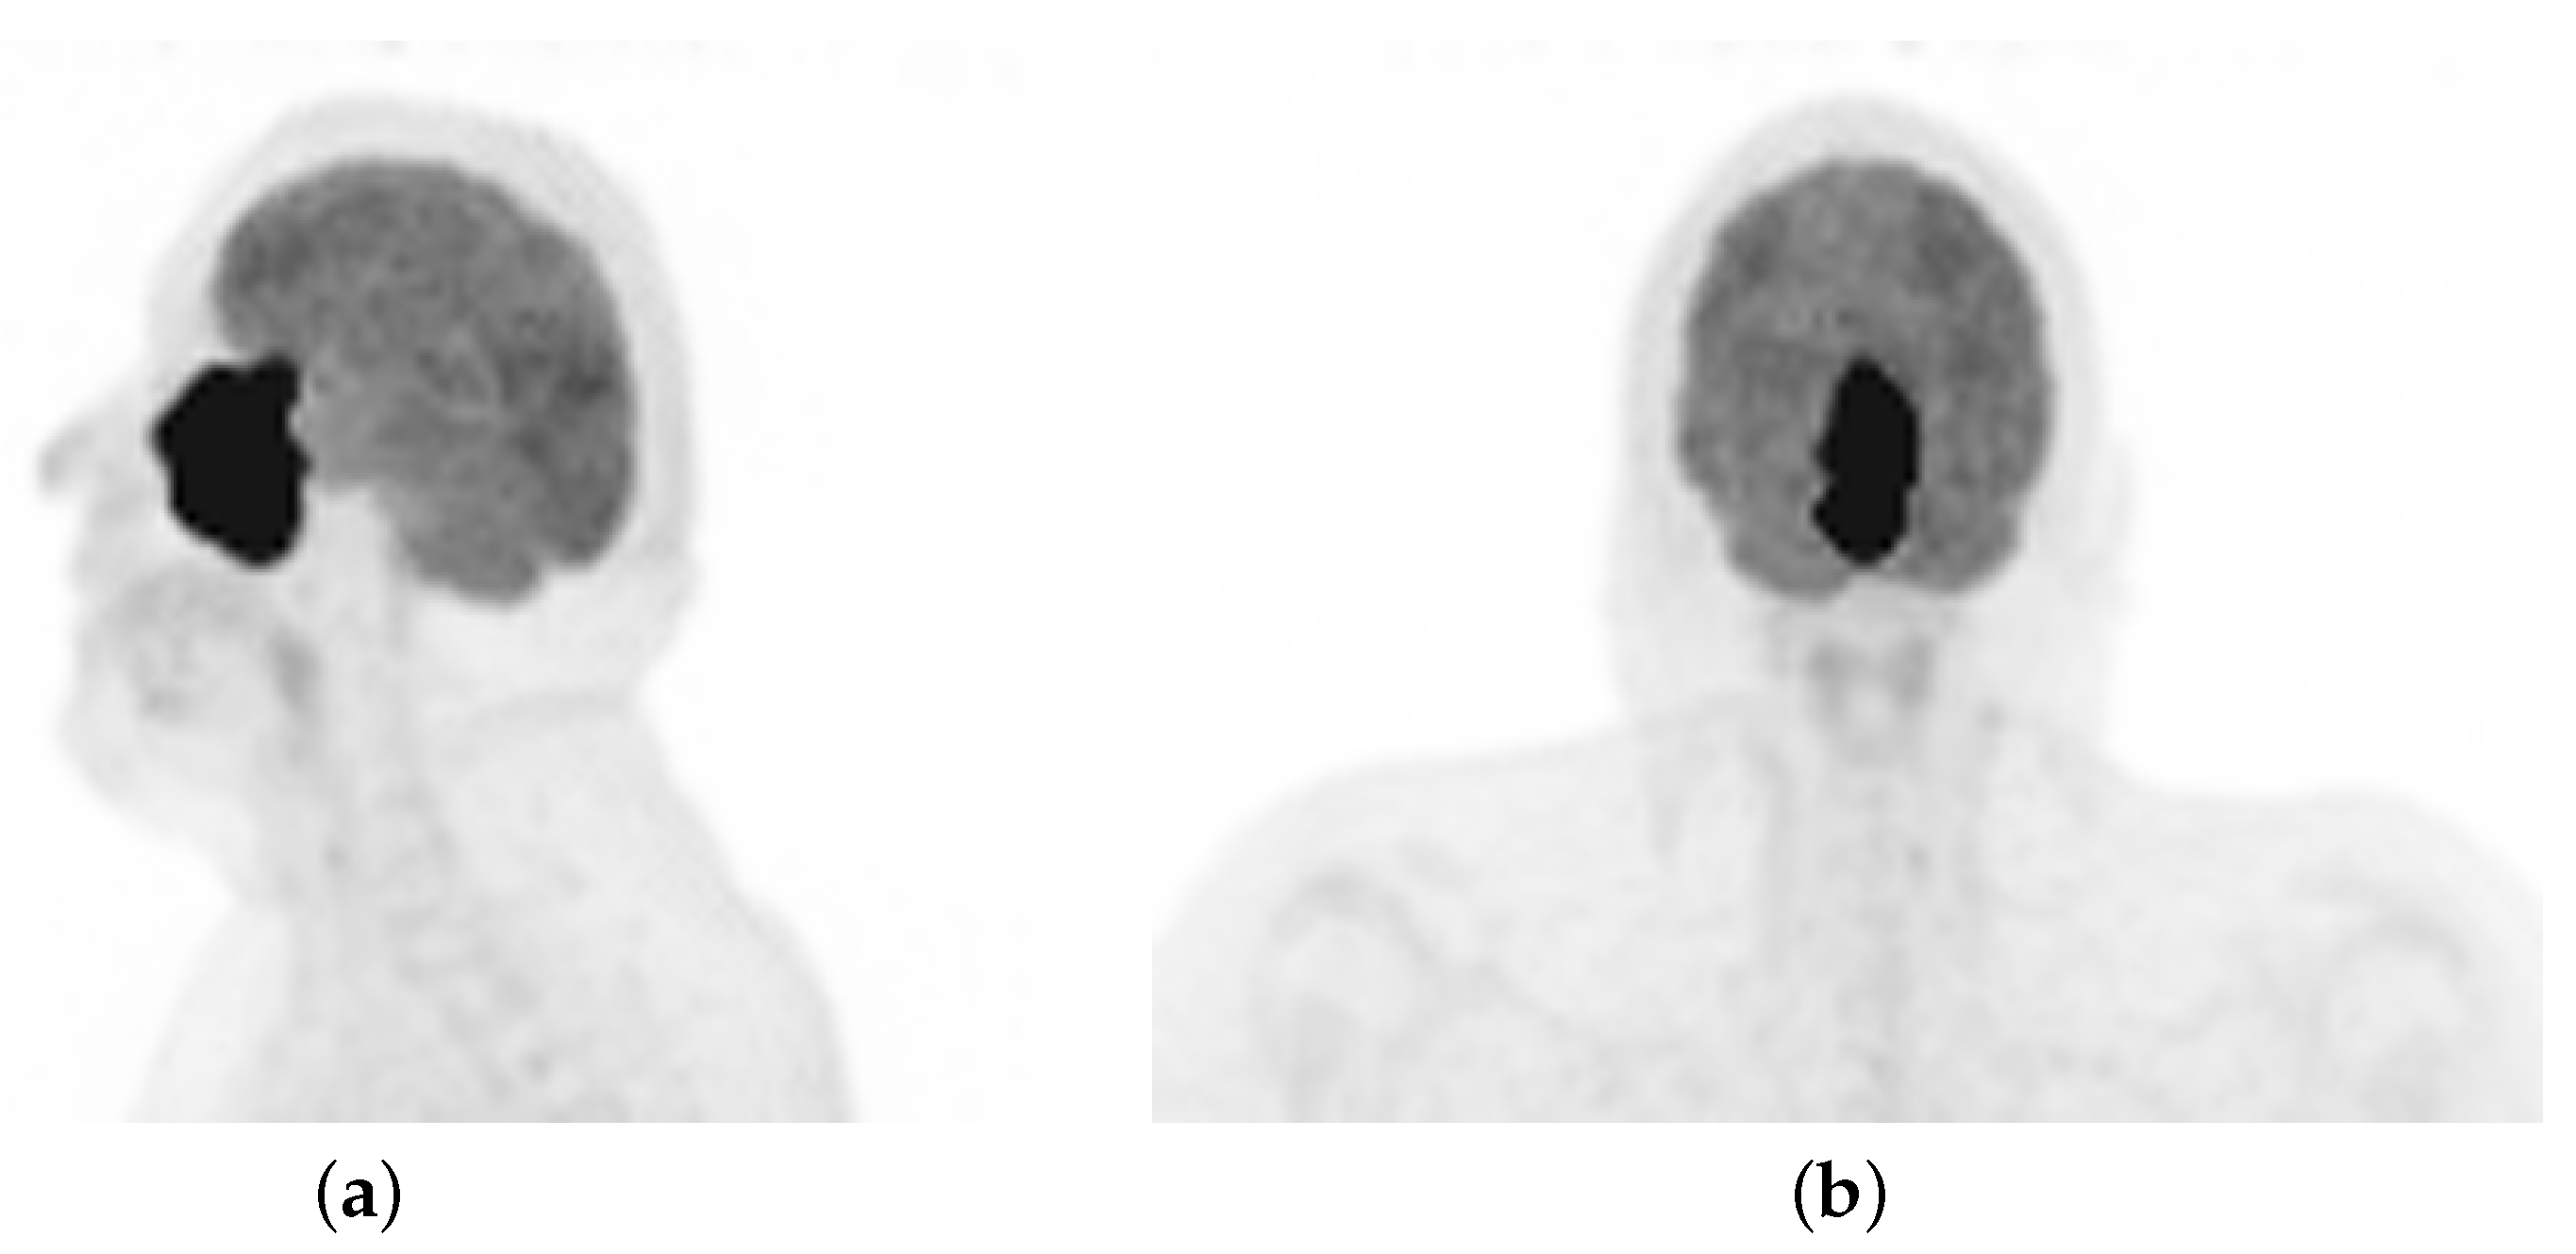

A 48-year-old non-smoker male patient presented with nasal obstruction for over a year. A computed tomography (CT) scan and magnetic resonance imaging (MRI) revealed a large, infiltrating mass involving the left nasal cavity (Figure 1) and ethmoid sinus, extending into the periorbital fat and brain parenchyma at the level of the right gyrus. Biopsy and histopathologic examination led to the diagnosis of SNUC (Figure 2a) with increased H3K27 trimethylation (Figure 2b), compatible with the hypermethylated phenotype. It was classified as stage cT4b based on the radiological findings. Molecular profiling on the biopsy sample showed a previously not reported mutation of IDH2 (R172A) and a common TP53 mutation (R273H) [8,9]. A positron emission tomography (PET) using [18F]fluorodeoxyglucose ([18F]FDG) highlighted an intense hypermetabolism of the lesion (Figure 3) without evidence of metastasis. Following the diagnosis, the patient underwent three cycles of neoadjuvant chemotherapy composed of a combination of docetaxel, carboplatin, and 5-fluorouracil (TCF). The lesion was thereafter surgically removed following 3 months of treatment. The pathological examination of the surgical specimen showed important post-treatment remodeling, indicating a good response to chemotherapy and showing only a few residual tumor cells in the nasal septum, spanning 0.6 mm on its longest axis (ypT1). No evidence of loco-regional or distant metastasis was found.

Figure 3. [18F]FDG PET maximum intensity projection showing a large, irregular and intensely hypermetabolic mass in the sinonasal region. (a) lateral view. (b) frontal view.